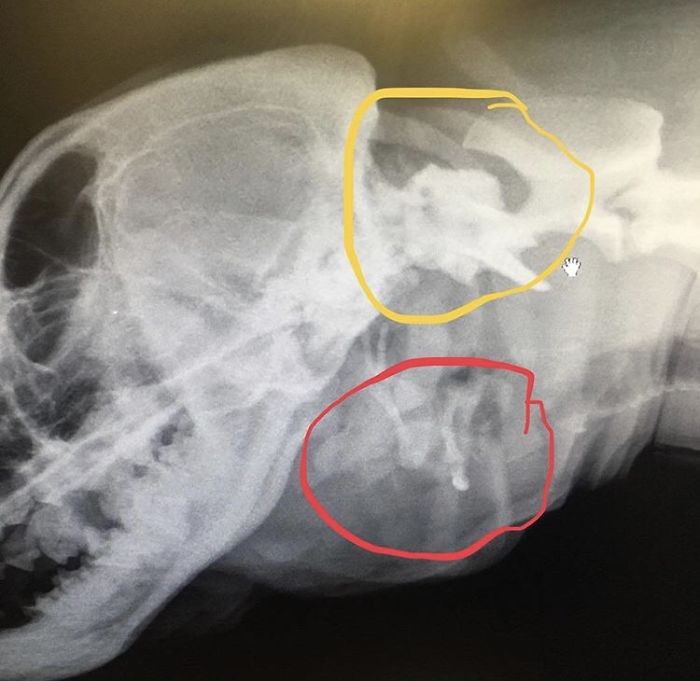

We took more X-rays of Toad’s skull. Now that we have had Toad for a long time and learned about her issues more than when we first met her, we are able to understand the X-rays a bit better. The first image shows how wonky her skull is shaped. She has an extra orbital bone around her eye socket, likely from the skull of the twin she absorbed in utero, which makes her skull extra bulbous. The red circle shows two sets of hyoid bones. The yellow shows how the vertebrae aren’t attached the way they are supposed to be. The green circle shows her extra trachea, which is not fully formed.